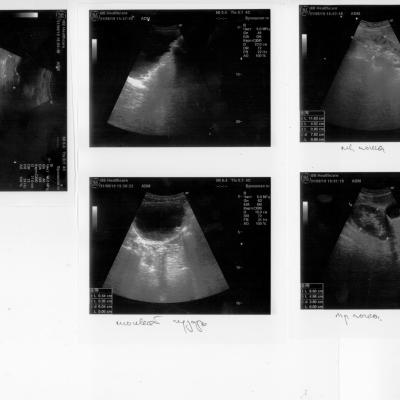

Здравствуйте. Травма С5 в 2003 г. Разница между обследованием 2, 2.1, 2.2 и 1, 1.1, 1.2 одна неделя. Остаточная моча 500-600мм. Уролог сказал, что надо ставить эпицистому, лечащий врач нейрохирург посоветовал не спешить, поставить катетер фолея на дней 10 опорожняя мочевой через каждые 5-6часов. У меня хр. цистит, хр. пиелонефрит. Посоветуйте пожалуйста что делать в данной ситуации? С уважением Руслан.